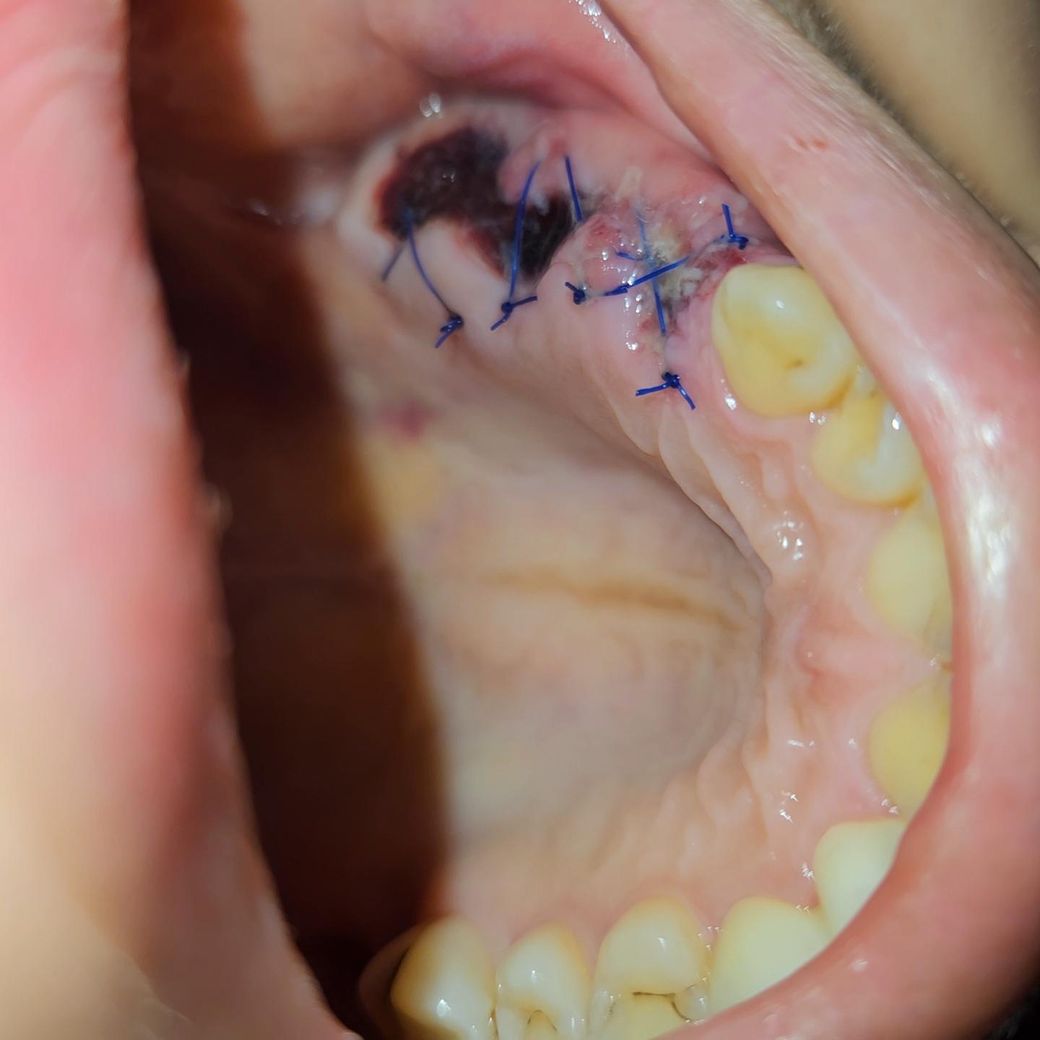

• 2번 째 사진

• 사진 보니 새살 올라 오는거 같기도 하고.. 염증같기도 하고...

사진상에 보이는건 잇몸이 치유되면서 생기는 자연스러운 현상이니 크게 걱정은 안하셔도 될것같습니다.

5월 20일 임플란트 심은 것은 정상적으로 아물고 있는 것으로 보입니다. 토요일 가 실밥 풀면 될 것으로 보입니다.

너무 불안해서 먼저 질문 글 드립니다 ㅠㅠ -> 사진으로 봤을때 염증의 양상은 아닙니다